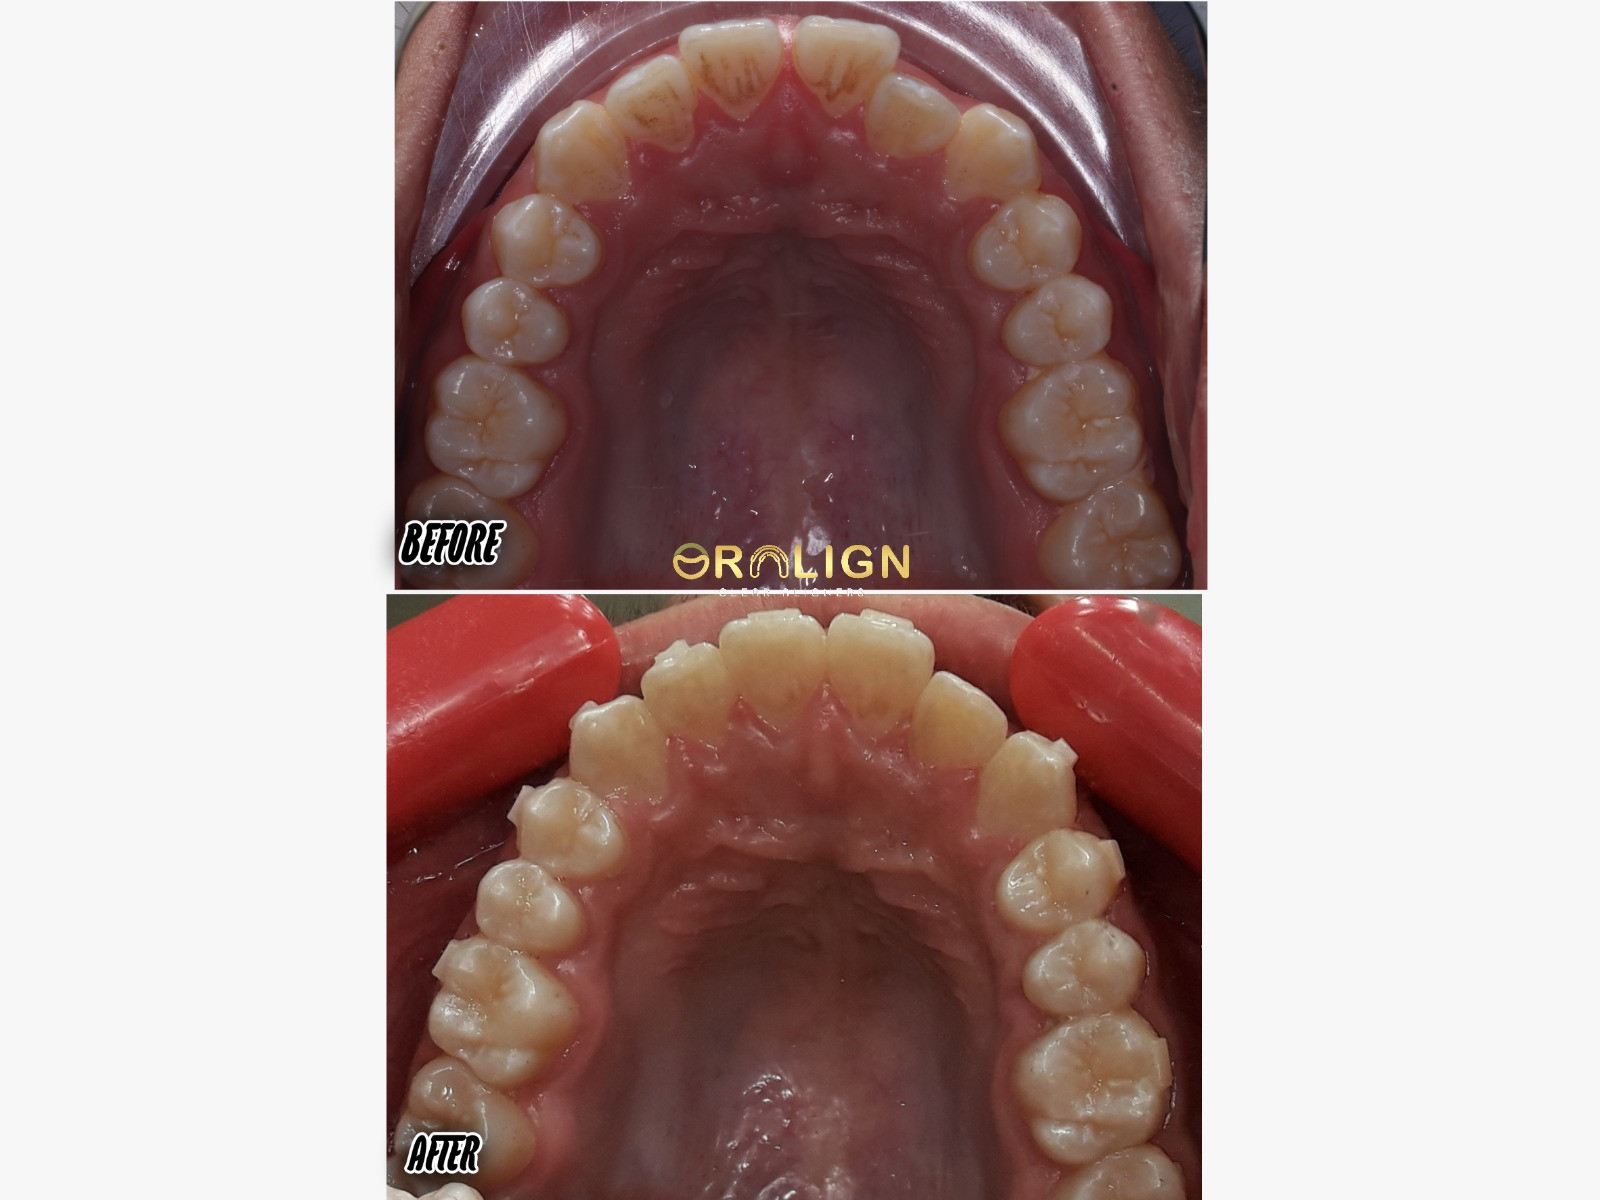

نتائج موثوقة

استعد ثقتك من جديد

شاهد نتائج حقيقية مع آلاف الحالات الناجحة التي حققنا معها المستحيل.